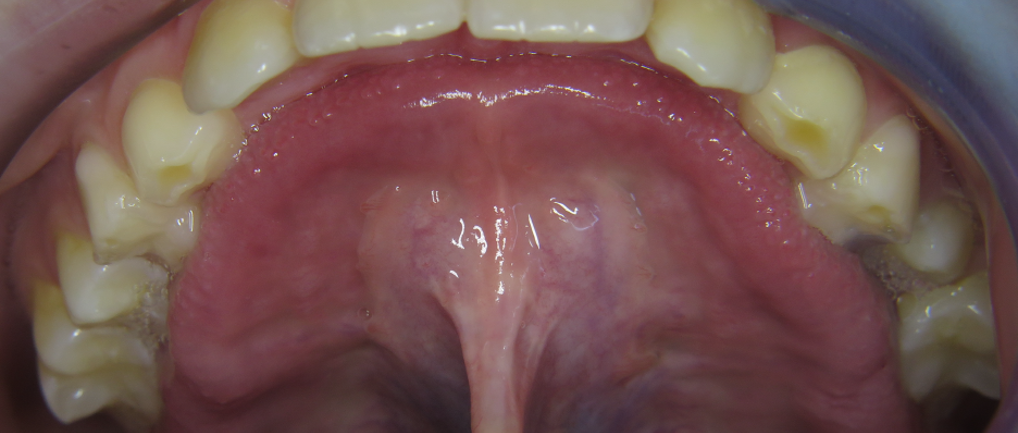

Aus diesem Grund legen Kieferorthopäden und Logopäden, die mit mykie® arbeiten, in der Diagnostik besonderen Wert auf die Zungenfunktion – und damit das Zungenband. Die Zunge stabilisiert den Oberkiefer von innen und formt den Zahnbogen aus (siehe Foto). Nur so finden alle Zähne Platz! Für weiterführende Informationen rund um das Zungenband klicken Sie bitte hier.

Diese Galerie zeigt verschiedene Problemstellungen rund um das Zungenband von Anfang bis Ende der aktiven Behandlung: